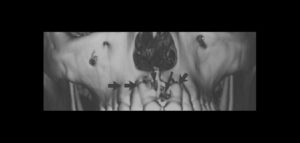

El número de pacientes que requieren prótesis sobre implantes ha aumentado considerablemente en los últimos años. La osteointegración de los implantes dentales es el requisito